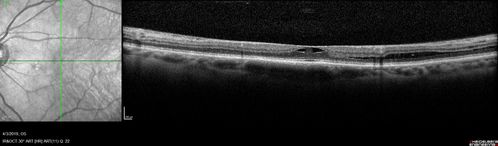

Stellate Non-heredtiary Idiopathic Foveomacular Retinoschisis (SNIFR)

77 year old man who is healthy and 6'6" tall with 20/40 vision and no complaints. OCT shows diffuse retinoschisis.